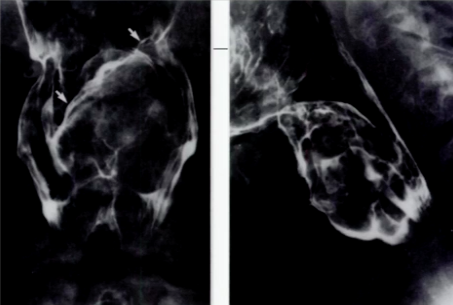

What could be causing the sign shown below?

An advanced carcinoma. Note the multiple filling defects with ulcerations.

What causes this?

Weakness of muscular layer (cricopharyngeaus) in the esophagus that allows mucosa to protrude through and form a Zenker Diverticulum.

What type of diverticulum originates inferior to the cricopharyngeus?

Killian-Jaimeson Diverticulum